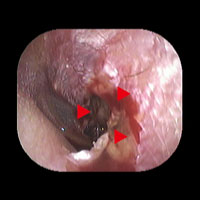

左外傷性鼓膜穿孔

患者様が耳かき中に誤って、左の鼓膜を破ってしまいました。赤い矢頭で囲まれた部分に穿孔(穴)があります。ほとんどの場合、自然に閉鎖します。この症例では12日目に閉鎖しました。3カ月経過しても自然に閉鎖せずに難聴などがあれば、鼓膜閉鎖術をお勧めします。

初診日